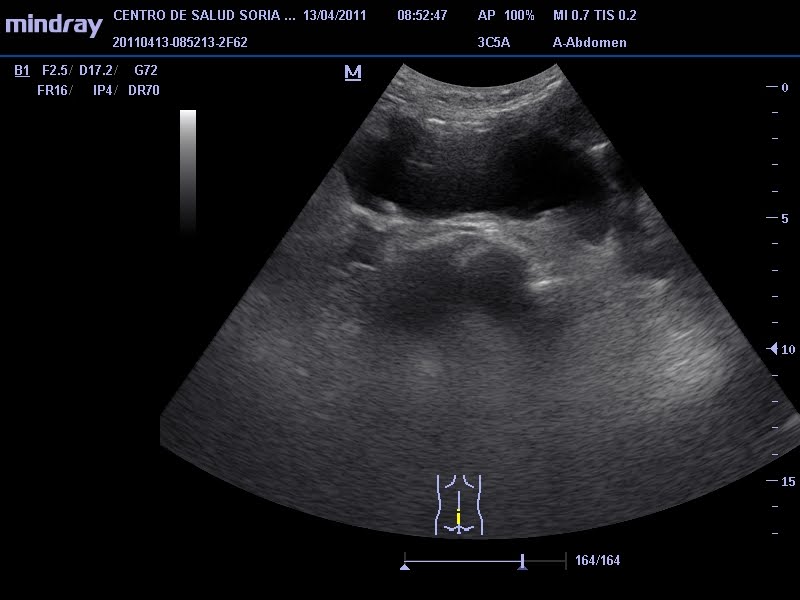

Primera Eco Tras Beta Positiva, De la Beta positiva a la primera ecografía. Unas semanas difíciles de gestionar., 5.91 MB, 04:18, 4,799, C'Est La Vie, Noemí!, 2020-03-12T13:32:38.000000Z, 3, Valores Beta Positiva Fiv Discount Buy, Save 42% | jlcatj.gob.mx, www.jlcatj.gob.mx, 1200 x 1600, jpeg, WebLos primeros días después de una beta positiva suelen ser de felicidad absoluta, pensamos que nuestro sueño se ha cumplido y que, por fin, después de. WebEscorpio, es imposible intuir a través de la beta si se trata de un parto múltiple o no. La mejor manera de saber si se trata de un embarazo múltiple es a través. Web¿Cuándo realizar la primera ecografía de embarazo tras los tratamientos de FIV? Se debe realizar entre la 5ª y la 7ª semana de gestación, es decir entre 3 y 5 semanas tras la., 20, primera-eco-tras-beta-positiva, Novedades y Muebles WebLos primeros días después de una beta positiva suelen ser de felicidad absoluta, pensamos que nuestro sueño se ha cumplido y que, por fin, después de. WebEscorpio, es imposible intuir a través de la beta si se trata de un parto múltiple o no. La mejor manera de saber si se trata de un embarazo múltiple es a través. Web¿Cuándo realizar la primera ecografía de embarazo tras los tratamientos de FIV? Se debe realizar entre la 5ª y la 7ª semana de gestación, es decir entre 3 y 5 semanas tras la.

Web1era eco sin embrión y prueba positiva alguien igual? - Página 3: hoy he tenido mi primera eco en principio estoy de 6.6 pero no habiA embrión ni saco...me he. Web¡Hola de nuevo, preciosas!La #betaespera ha acabado y ya tenemos el resultado... #BetaPositiva :) :) :)¡Os lo cuento todo en el vídeo WebLa beta-hCG se empieza a detectar a partir de la tercera o cuarta semana de embarazo y se incrementa durante todo el primer trimestre. A partir de la semana 12,. Web5º- Semana 7: Todas te harán una eco para confirmar el latido del corazón y la mayoría te darán el alta. (El momento latido no lo vas a olvidar nunca) Como ves sólo hay consenso. WebHola a todas. El día 2 de marzo me hice la transfer del único embri que conseguí en mi primera ICSI. El día 16 me hicieron la beta y dio positivo, así que me. WebLa primera ecografía tras conocer el embarazo es un momento inolvidable y crucial, sobre todo si se produce tras un Tratamiento de Fecundación In Vitro. Aunque los. WebAunque el análisis de la beta hCG en sangre haya dado positivo, normalmente hasta al menos la semana 6 de embarazo no se empieza a ver nada en la. WebHola lunita, claro que lo importante es que la beta esté bien. Y además despues de 7 intentos es mi primer positivo. Solo quiero hacer como un estudio de betas.